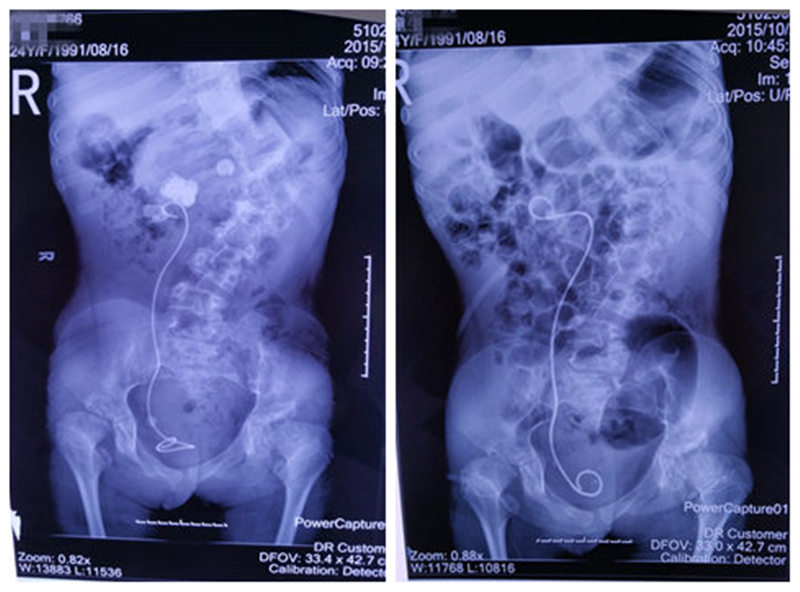

患者尿路平片手术前后对比